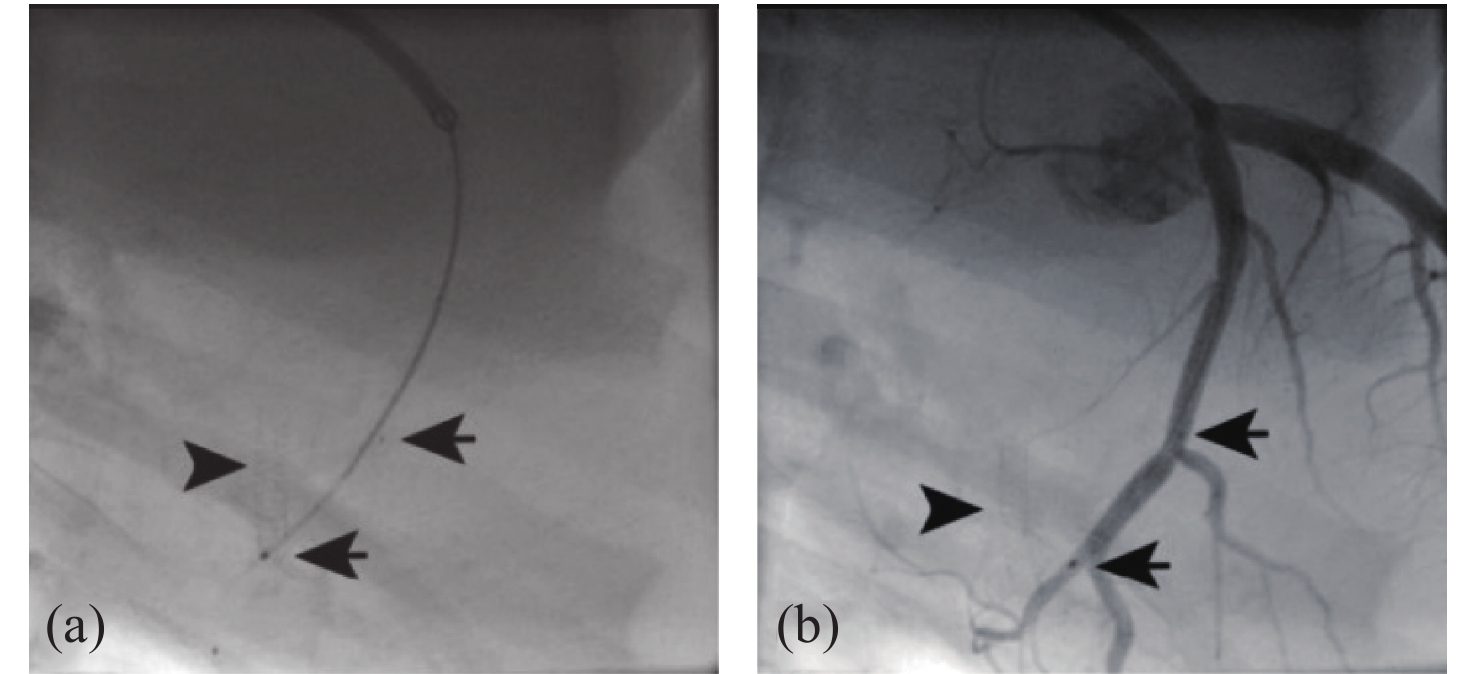

Optical Coherence Tomography (OCT) is a new imaging technique that uses interference in low coherent light by measuring the delay and magnitude of backscattered or reflected signals from the sample. OCT technology can provide real-time structural information with one-dimensional depth and two- and three-dimensional tomography at micron-scale resolution. Besides its high spatial resolution, OCT imaging is beneficial for its non-contact and non-invasive methodology. The system is also easy to operate and relatively portable. OCT technology is mainly applied in the biomedical imaging field for diagnoses, making up for the shortcomings of the low penetration depth in confocal microscopes and the low resolution in ultrasonic imaging. At present, OCT technology has been used as the clinical standard for the diagnosis of retinal diseases, and the combination of OCT technology and endoscope technology has become an important tool for the clinical diagnosis of cardiovascular and gastrointestinal diseases. It also provides references for early cancer diagnosis, surgical guidance and postoperative rehabilitation of musculoskeletal diseases. To broaden the application of OCT technology and improve its medical detection capabilities, researchers are committed to increasing the penetration depth of OCT imaging in biological tissue, improving the system's resolution and signal-to-noise ratio, and optimizing its overall performance. This review introduces the principle and classification of OCT systems, their applications and their recent progress in various biomedical fields.